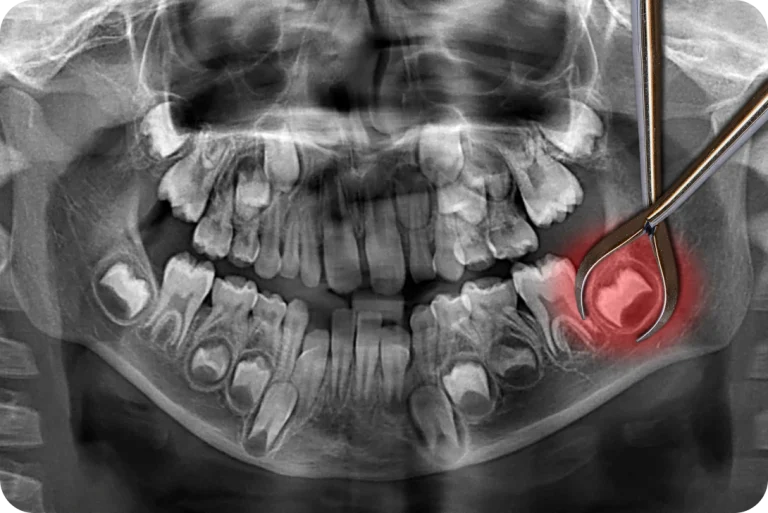

L’implantologie permet de replacer une dent en cas de maladies dégénératives, d’infections, de traumatismes ou autres. Un dispositif, appelé l’implant, permet de remplacer la racine de la dent manquante. Une couronne sera alors placée sur cet implant pour remplacer la partie extérieure de la dent. Notre dentiste à Toulouse peut traiter les cas avancés nécessitant une ou plusieurs extractions bucco-dentaires et vous permettre de retrouver l’intégrité de votre denture après une carie ou un choc.